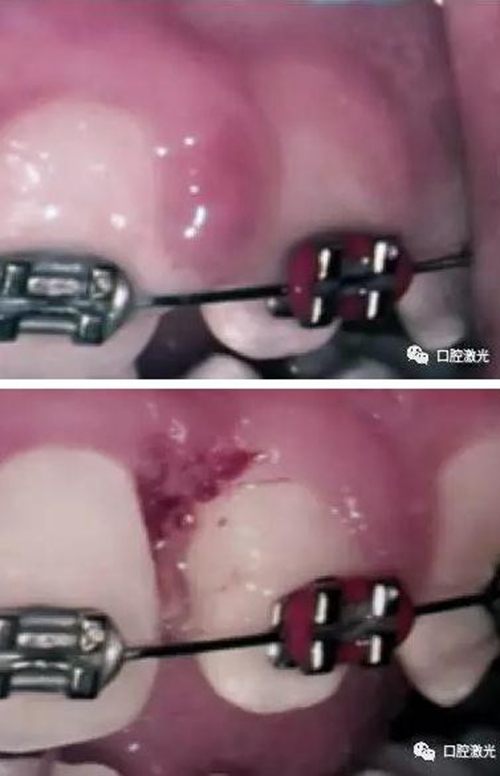

表麻下牙齦增生的激光切除即可效果